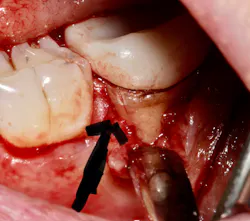

Root fracture is a common source of pain after root canal treatment and is of particular concern since it may be hard to diagnose (figure 1).5 Although new technologies such as three-dimensional imaging and microscopes have increased diagnostic ability, vertical fractures can still be hard to ascertain. Isolated periodontal pockets and a history of sharp pain that progresses to a dull throbbing pain upon mastication/palpation are common signs of fracture. Other common risk factors for fracture include: the lower second molar (most likely tooth to fracture), parafunctional habits including clenching/bruxism, large amalgam restorations, thermal injury, psychological stress, teeth with existing erosion, abrasion, and/or abfraction. A fractured tooth may need to be extracted to alleviate symptoms of pain (figure 2).